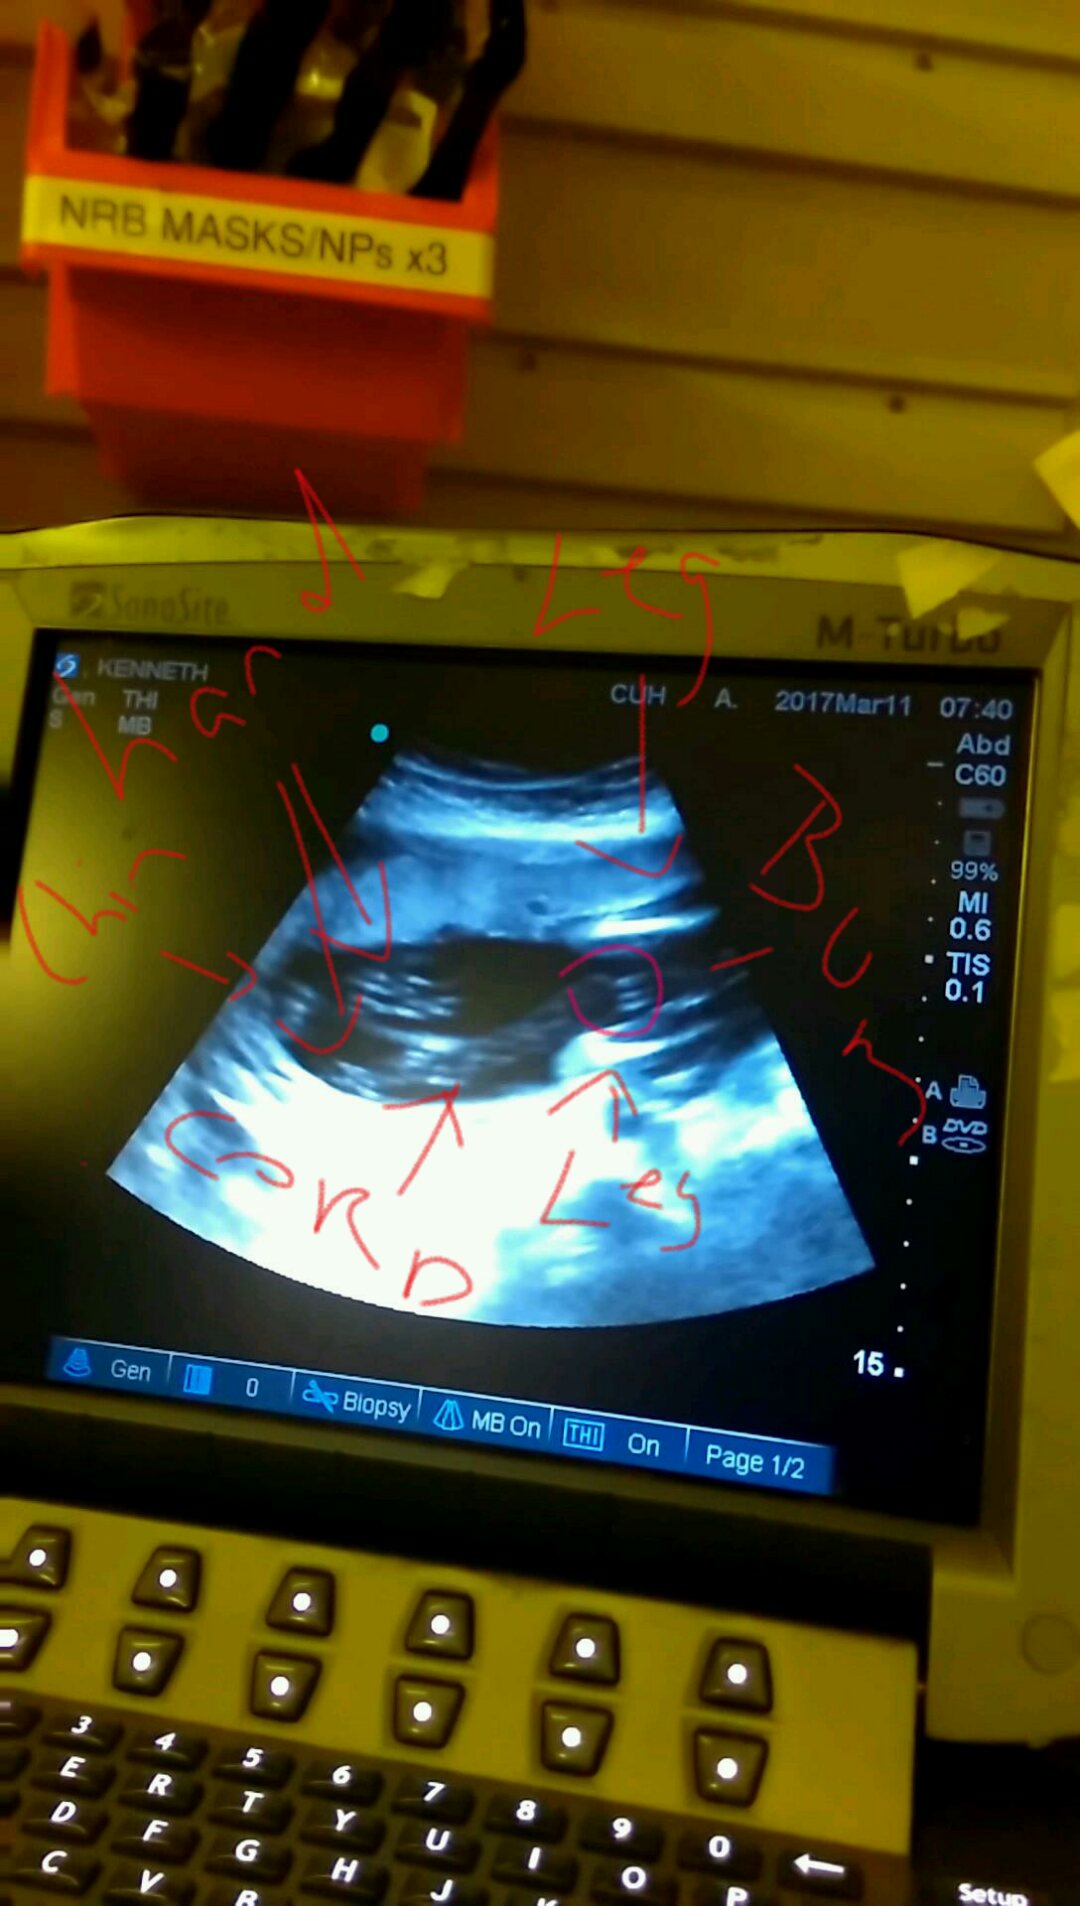

I'm guessing a girl but it's a hard one. Anyone guess this one? It's @ 19+2. Looks girlie but @ 15+4 had a scan and there was a bright white thing dangling between the legs from front view that looked all boy. Attachment 35361